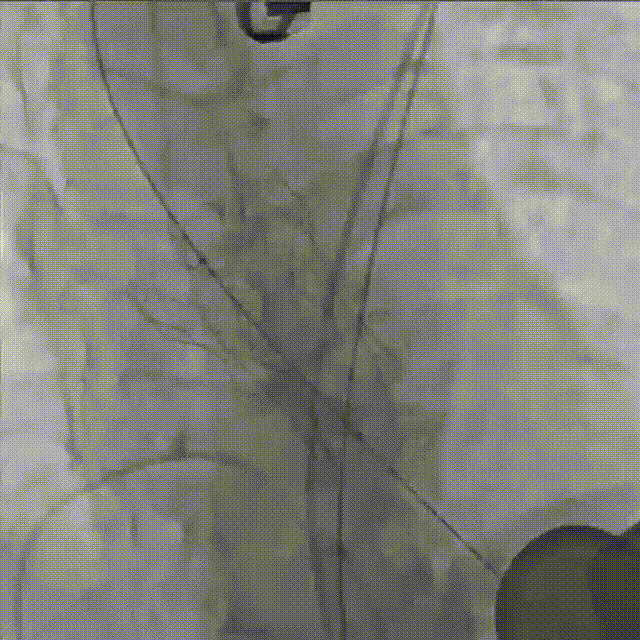

手术关键步骤

E.球囊后扩

F. 最终造影

术后即刻评估

术后即刻TEE示主动面瓣膜最大峰值血流速为2.1 m/s,平均跨瓣压差为8.6 mmHg,少量瓣周漏。